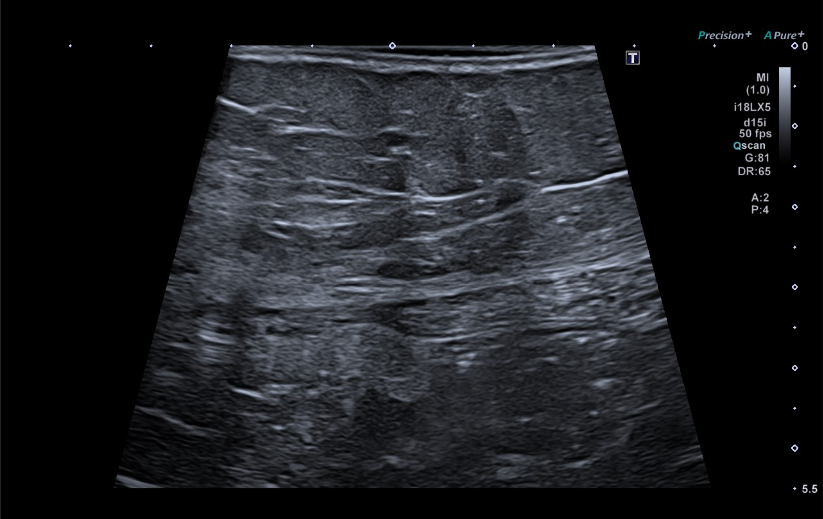

Se realiza una ecografía abdominal en el centro de salud visualizándose una masa hiperecogénica de 15 centímetros, aproximadamente, que parece dependiente del riñón derecho.